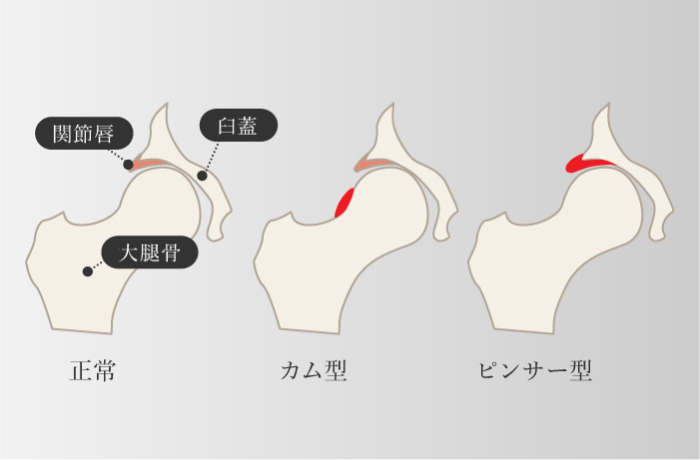

インピンジメント症候群・FAI

大腿骨寛骨臼インピンジメント

-

先天性のものと後天性のもの2種類があり、先天性の構造要因には、大腿骨頭や寛骨臼の形成不全がある。 また、後天性の構造的要因の代表例には、変形性股関節症があり、軟骨の摩耗や骨棘の形成により、股関節のインピンジメントが発生する。